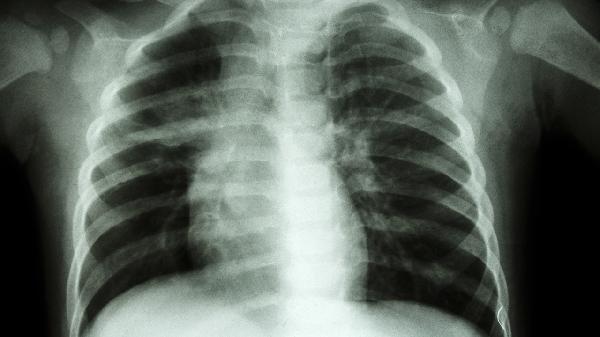

胸椎骨折恢复期需严格卧床6-8周,使用硬板床并避免弯腰动作。饮食应增加牛奶、豆制品等高钙食物,适量补充维生素K2帮助钙沉积。三个月内禁止提重物,逐步进行腰背肌功能锻炼如五点支撑法。定期复查X线观察骨痂形成情况,若出现下肢麻木或排便异常需立即就诊。